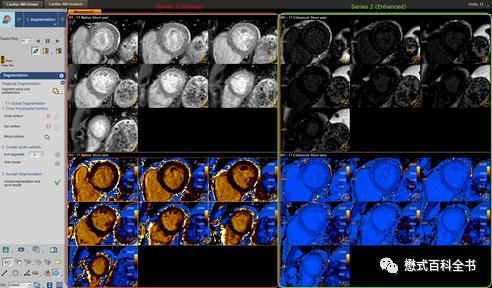

图19、20:工作站处理T1 mapping图